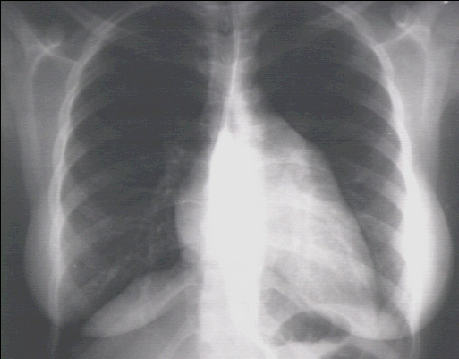

These chest X rays show left ventricular enlargement and left atrial enlargement. This PA view demonstrates the enlarged left ventricle as an increase in the inferolateral cardiac border associated with an increased cardiothoracic ratio.

The markedly enlarged left atrium is manifested by the double contour within the heart border, an elevated left left mainstem bronchus, and an enlarged left atrial appendage.